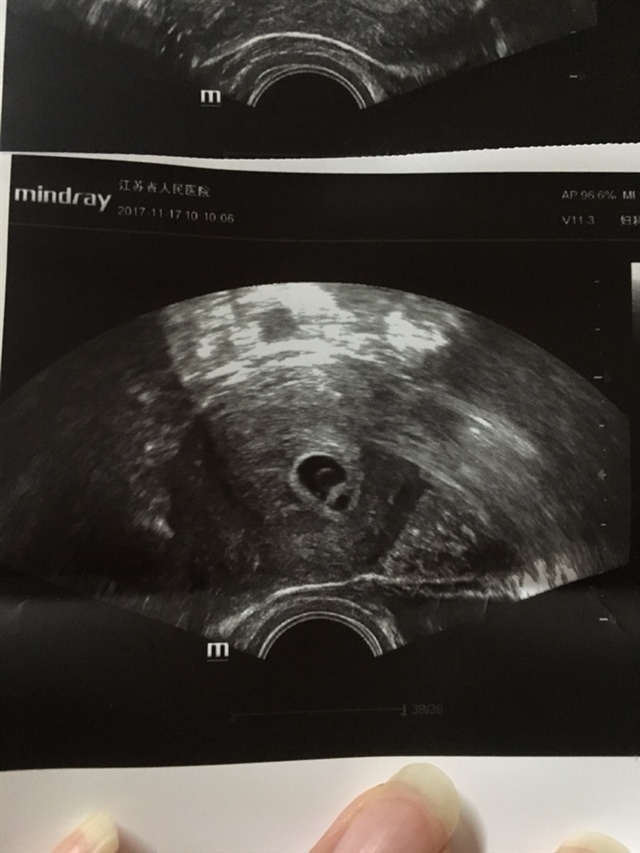

孕8周+1天

有胎心胎芽说明是活的。

董小姐全球购[帖主]:正在发育中……

上周还未见胎牙,今天发现宝宝发芽了